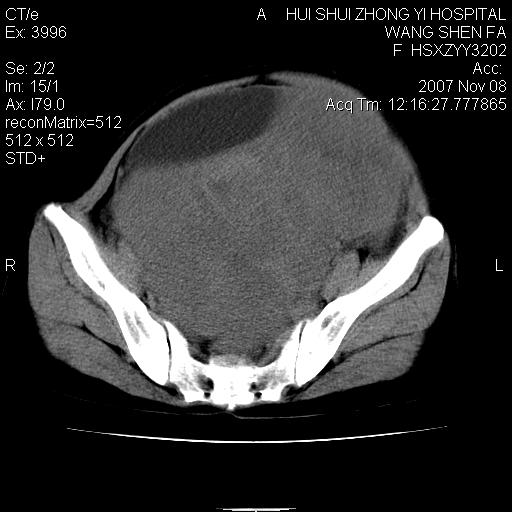

标题: CT10389:女,38岁,腹部巨大包块 [打印本页]

标题: CT10389:女,38岁,腹部巨大包块

腹部巨大包块半年,质硬,边界不清。

下腹部巨大软组织影,密度不均匀,并可见分隔,病灶边缘较清,肠管受压移位。子宫未显示。盆腔、双侧腹股沟未见明显肿大淋巴结。考虑:1.卵巢病变可能性大,囊腺癌>卵巢癌>囊腺瘤.2.多发性阔韧带子宫肌瘤待除外.

盆腔及下腹部多发肿块,密度不均,与子宫关系密切,周围肠管受压改变,盆腔内未见肿大淋巴结,考虑多发性巨大子宫肌瘤可能。直接手术吧!

下腹部巨大软组织影,密度不均匀,并可见分隔,病灶边缘较清,肠管受压移位。病灶下部与子宫及附件关系密切。盆腔、双侧腹股沟未见明显肿大淋巴结。考虑:1.卵巢实质性肿瘤可能性大,卵巢癌>颗粒细胞>卵泡膜细胞瘤>纤维瘤.2.多发子宫肌瘤待除外.

膀胱向前明显的推压移位,子宫增大明显,肠管推压移位,未见明显的侵润;患者女性,育龄期,考虑多发子宫肌瘤可能性大

看病变像是起源于双侧的附件,还是考虑卵巢囊腺瘤,不排除囊腺癌